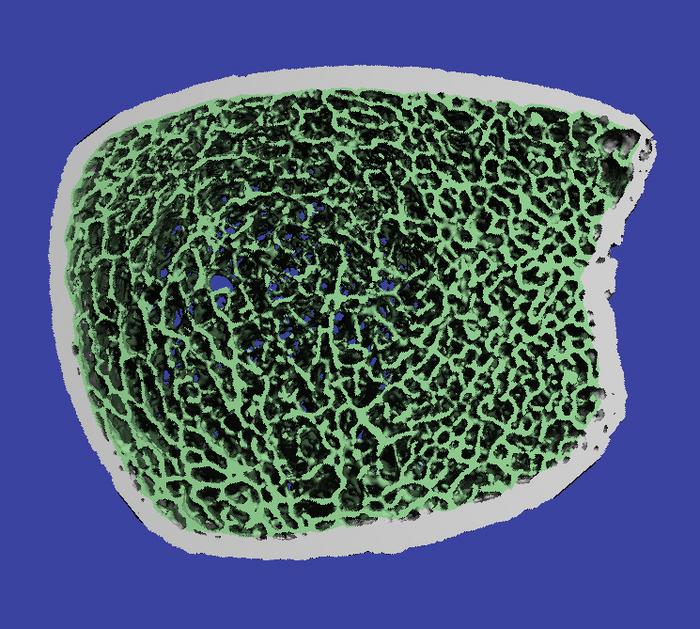

The HR-pQCT scanner is a state-of-the-art device, recently installed at Atrium Health Wake Forest Baptist Medical Center and the first in North Carolina, that uses a low-radiation approach to assess bone mineral density and bone microarchitecture.

“Unlike other available imaging, HR-pQCT allows high-resolution novel image processing techniques that can provide precise images with detailed characterization of bone,” Weaver said. “By analyzing this bone microarchitecture, we have valuable insight into fracture risk and skeletal fragility.”

“We are able to combine this high-resolution imaging with computational modeling to understand how bone strength changes following surgery and in response to the intervention,” said Caitlyn Collins, Ph.D. , assistant professor of biomedical engineering and mechanics at Virginia Tech and a co-investigator on the ancillary study to the STRONG BONES trial. “This gives us a more in-depth understanding of how and where risedronate may be affecting bone remodeling in our study participants.”